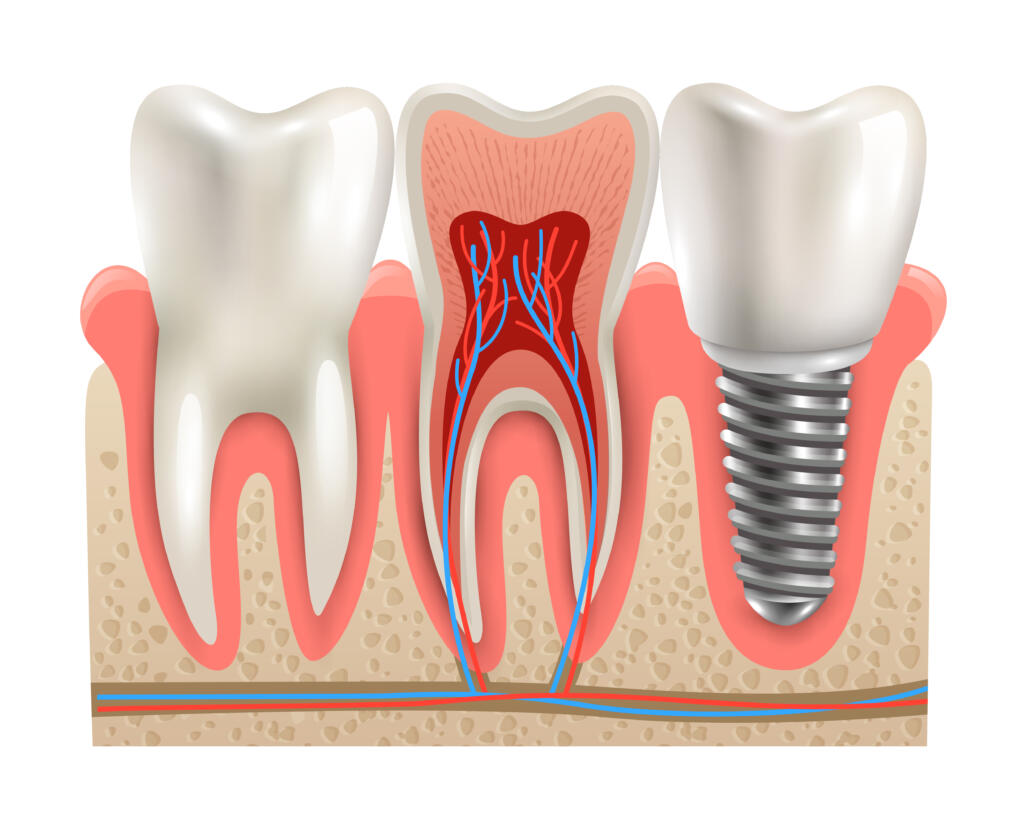

İmplant eksik dişlerin tedavisinde kullanılan ve çene kemiğinin içine yerleştirilen titanyumdan yapılmış vidalardır. Bu vidaların üzerine diş protezi yerleştirilir. İmplant tedavisinin diğer tedavilere avantajı komşu dişlere zarar verilmez. Yani komşu dişlerin kesilmesi gerekmez. İmplant diş kök görevi görür ve doğal diş gibi rahatlıkla yemek yiyebilir, konuşabilir ve gülebilirsiniz.

İmplant tedavisi hastaya hafif bir lokal anestezi verilerek yapılır. İşlemden önce detaylı muayene ve röntgen gereklidir. Çene kemiklerinin ve kalan dişlerin ölçüsü alınır. Dental implantların yerleştirilmesi için iki seçenek vardır. Tek aşamalı işlemde implant yerleştirildikten sonra geçici başlık takılır. İki aşamalı işlemde ise dental implant takıldıktan sonra üzeri diş eti ile kapatılır ve iyileşmeye bırakılır. Protez başlıklar daha sonra takılır. Her iki durumda da geçici bir köprü yerleştirilir ve alt çene için 3 ay, üst çene için altı ay iyileşme süreci beklenir. Bazen dental implantların üzerine yeni yapılan dişler hemen takılabilir. Dental implantla hasta güvenle gülebilir ve yemek yiyebilir.